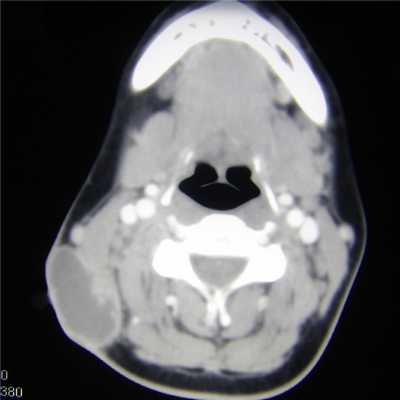

Для подтверждения/исключения онкопроцесса используют компьютерную томографию с контрастом и тонкоигольную (FNA) биопсию слюнных желез. В отдельных случаях возможно проведение МРТ. Проведение биопсии FNA обязательно, морфологическая диагностика позволяет определить степень необходимой хирургической резекции. Если в ходе диагностики не обнаружено злокачественности, цель операции заключается в удалении наружной доли железы (поверхностная паротидэктомия). При обнаружении злокачественности требуется более обширная хирургическая процедура, которая включает в себя удаление всей околоушной железы (общей паротидэктомии) и очистки лимфатических узлов.

В зависимости от диагноза, перед операцией назначаются различные исследования — УЗИ, компьютерная или магнитно-резонансная томография, рентгенография легких. В случае опухоли также необходима биопсия для выяснения характера образования. Слюннокаменная болезнь исследуется с помощью контрастной сиалографии.